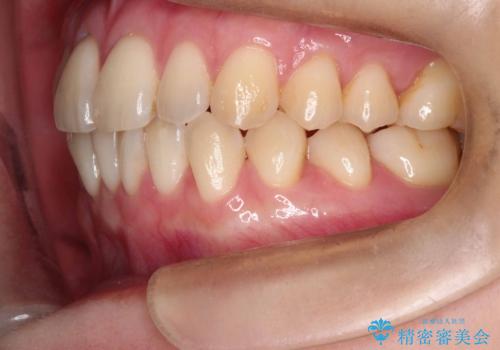

- 「下の前歯が斜めになっている」を主訴に来院された患者様です。

下顎前歯に叢生があり、右上2は反対咬合の状態でした。

下顎前歯の叢生がとれ右上2の反対咬合も改善し患者様にも満足していただけました。治療期間は1年~1年半を見込んでいましたが、患者様の協力もあり10か月で矯正を終えることが出来ました。